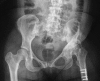

Background: Developmental dysplasia of the hip (DDH) is a leading cause of total hip arthroplasty (THA) in younger patients. It is unknown how the hospital costs of THA in patients with DDH compare with patients with degenerative arthritis.

Methods: This matched-cohort study included 354 patients undergoing primary THA for DDH and 1029 age-, sex-, and calendar year-matched patients undergoing THA for primary osteoarthritis between 2000 and 2008. DDH severity was measured by the Crowe classification. An institutional database was used to calculate the cost of care. Using line item details (date, type, frequency, and billed charge) for every procedure or service billed at our institution for each patient, bottom-up microcosting valuation techniques were used to generate standardized inflation-adjusted estimates of the cost of each service or procedure in constant dollars. Generalized linear random effects models were used to compare length of stay and costs during hospitalization and the 90-day period after surgery. Query of a longitudinal institutional database was used to identify documented complications.

Results: Patients with DDH undergoing primary THA incurred higher hospital costs than patients with primary osteoarthritis (USD 16,949 versus USD 16,485, p = 0.012). Operating room costs (USD 3471 versus USD 3417, p = 0.0085) and implant costs (USD 3896 versus USD 3493, p < 0.001) were higher in the DDH group compared with the osteoarthritis group. Length of stay was not different between the two groups (4 versus 4 days, p = 0.46). Crowe 4 hips had higher hospital costs than Crowe 1 hips (USD 21,246 versus USD 16,345, p < 0.001) with an associated longer length of stay (5 days versus 4 days, p = 0.0011) and higher implant costs (USD 4380 versus USD 3788, p = 0.0012). There was no detectible difference in 90-day complications in the case group compared with patients undergoing THA for osteoarthritis.

Conclusions: Hospital cost of primary THA is approximately USD 450 higher in patients with DDH compared with osteoarthritis. Increased severity of dysplasia (Crowe classification) was associated with higher costs.